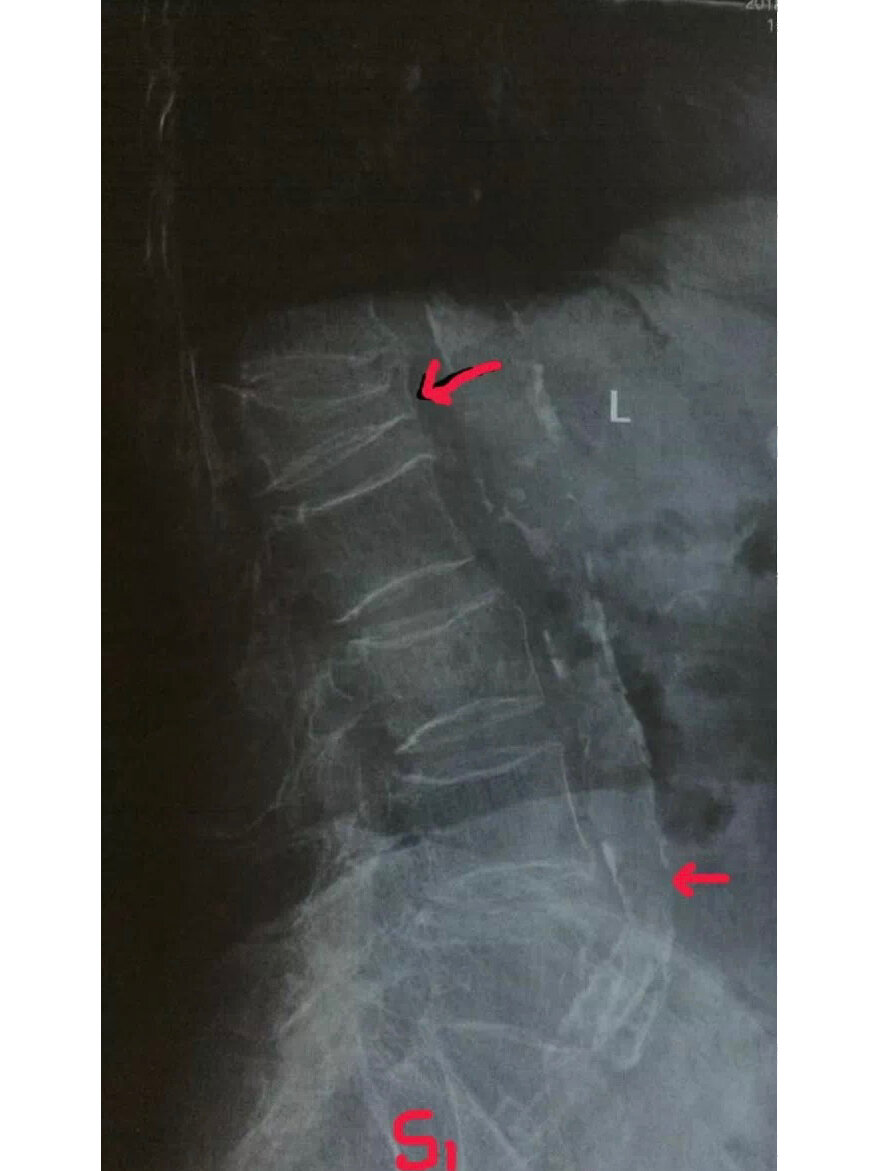

腹主动脉钙化,骨质疏松和l1压缩性骨折 转发同行照片.